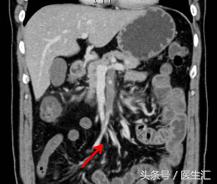

第7天凌晨2:00夜班医生查体全腹部平软,但是上腹部有一点点轻压痛,无反跳痛,麦氏点无压痛,夜班医师给与654-2解痉处理,但是效果还是不满意。所以做了一个中上腹CT平扫示:肠系膜上动、静脉周围渗出性改变,建议增强扫描。第7天早上10:00做中上腹增强CT示:肠系膜上动脉内低密度影,考虑附壁血栓形成,局部管腔重度狭窄。这个时候这个患者的诊断应该来说已经很明确了。于是请了相关科室的医生进行会诊,决定进行经皮选择性肠系膜动脉造影+肠系膜动脉溶栓术。患者溶栓导管行脉冲式注射尿激酶溶栓,患者术后24h出现便血4次,200ml/次。